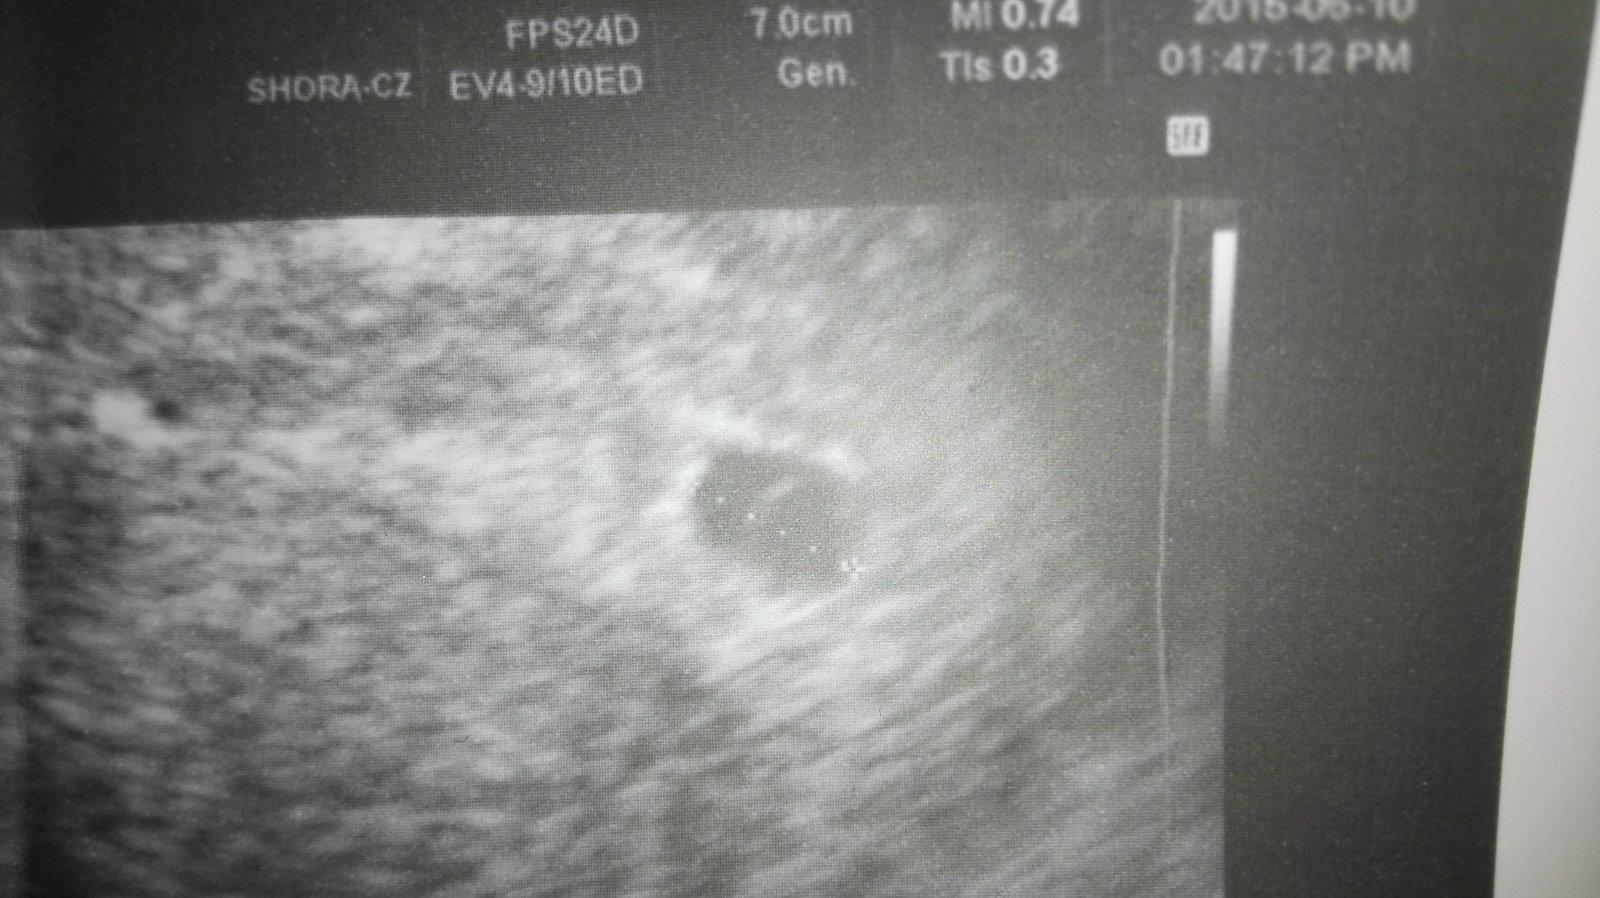

Můj gynekolog mě už od min týdne středy posílá ležet do nemocnice v pondělí sem u něho byla na kontrole a , že nevidí plod a srdíčko a že mám jít na krev hcg tak v pondělí mi jeden doktor na gynekologii říkal , že nevidí důvod at ležím tady , že mi nic není a je to mezi 5- 6 tt ve středu , že to roste , tak jak má zatím byl , tam jiný doktor. Dnes jsem šla znova do nemocnice a byl tam zrovna můj gynekolog a jsem z toho v šoku mi řekl , že je to nejspíš mimoděložní , že prostě zatím sme bez plodu a že mám další gest vaček vedle vaječniku, a mám hcg něco přes 5000 málo to šlo nahoru nešlo to ani jednou tolik . Tak sem se ho ptala co mám dělat a on ,že mám být v nemocnici , že otazka času kdy mi to praskne a vykrvácím a že příjdu o vaječník , tak se ptám , jestli teda jestli sem těhotná a on , že jo ale že neví kde a že příjdu nejspíš o vaječník. No a tak sem se rozbrečela a šla k jinému doktorovi ten mi řekl že gest,váček je v děloze 100% a že mimo děložní to není a může to bát cysta , která zasobuje těhot.nebo co , že prostě může zmizet - 100 krát sem se zeptala , že jestli to je v děloze a on že joo , že se ještě nestalo aby byl gest vaček tam i tam . A pokud mě něco bude bolet hodně , na pravo že mám letet do nemocnice , ale zatím nevidí důvod. Jsem v šoku prostě a , že pokud se to nebude vyvíjet , že prostě bud to samo potratí nebo výškrab nic víc . foto zprávy a foto min týdne

19.6.2015 15:55Proč pokládáš nový - stejný dotaz? Jinak ve zpráve se píše,že břicho máš měkk3,prohmatné,bez rezistence- že nehmatá nic neobvyklého (bouli nebo tak). Pak je napsána výška sliznice a že gest.váček se nachází ve vejcovodu a doporučuje pobyt v nemocnici s odběry na měření hladiny hcg.. Nic co bys nepsala v předchozím dotazu